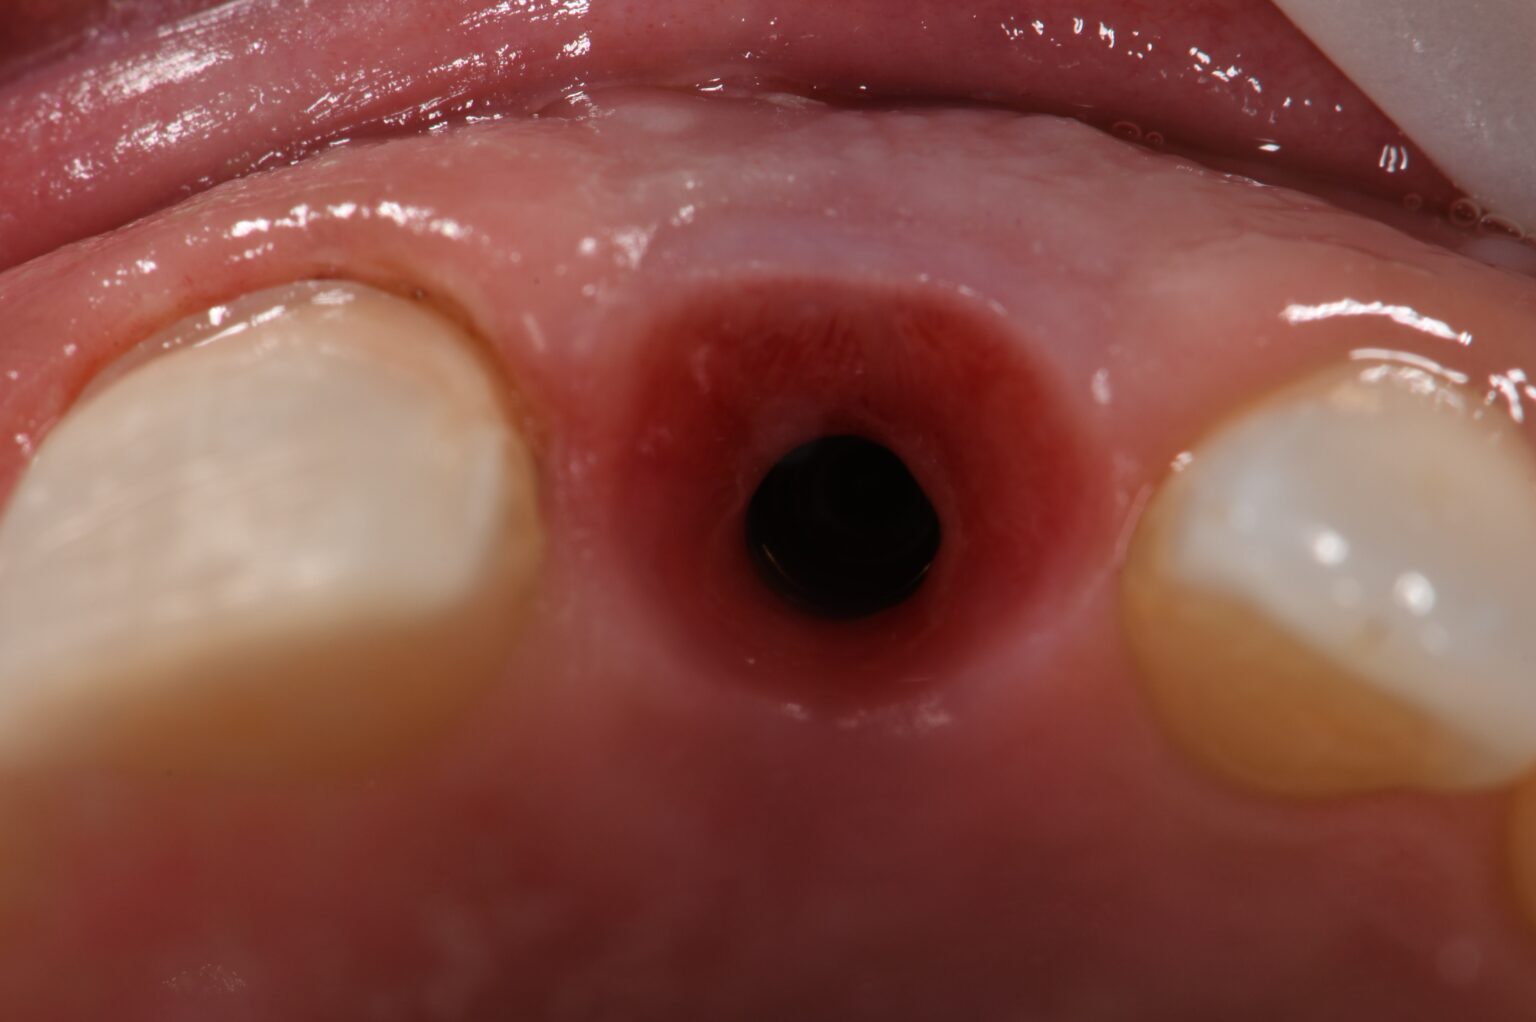

A) Occlusal clinical view of the implants placed in an ideal position Dental Implants Provisional Crown It is common practice to place a temporary crown first, pending the fabrication and placement of the permanent crown. The temporization of a dental implant following surgery, particularly in the anterior region, is a necessary procedure. They are normally made from a. A temporary crown is a good option to help with a patient’s current problem before a permanent crown. Dental Implants Provisional Crown.